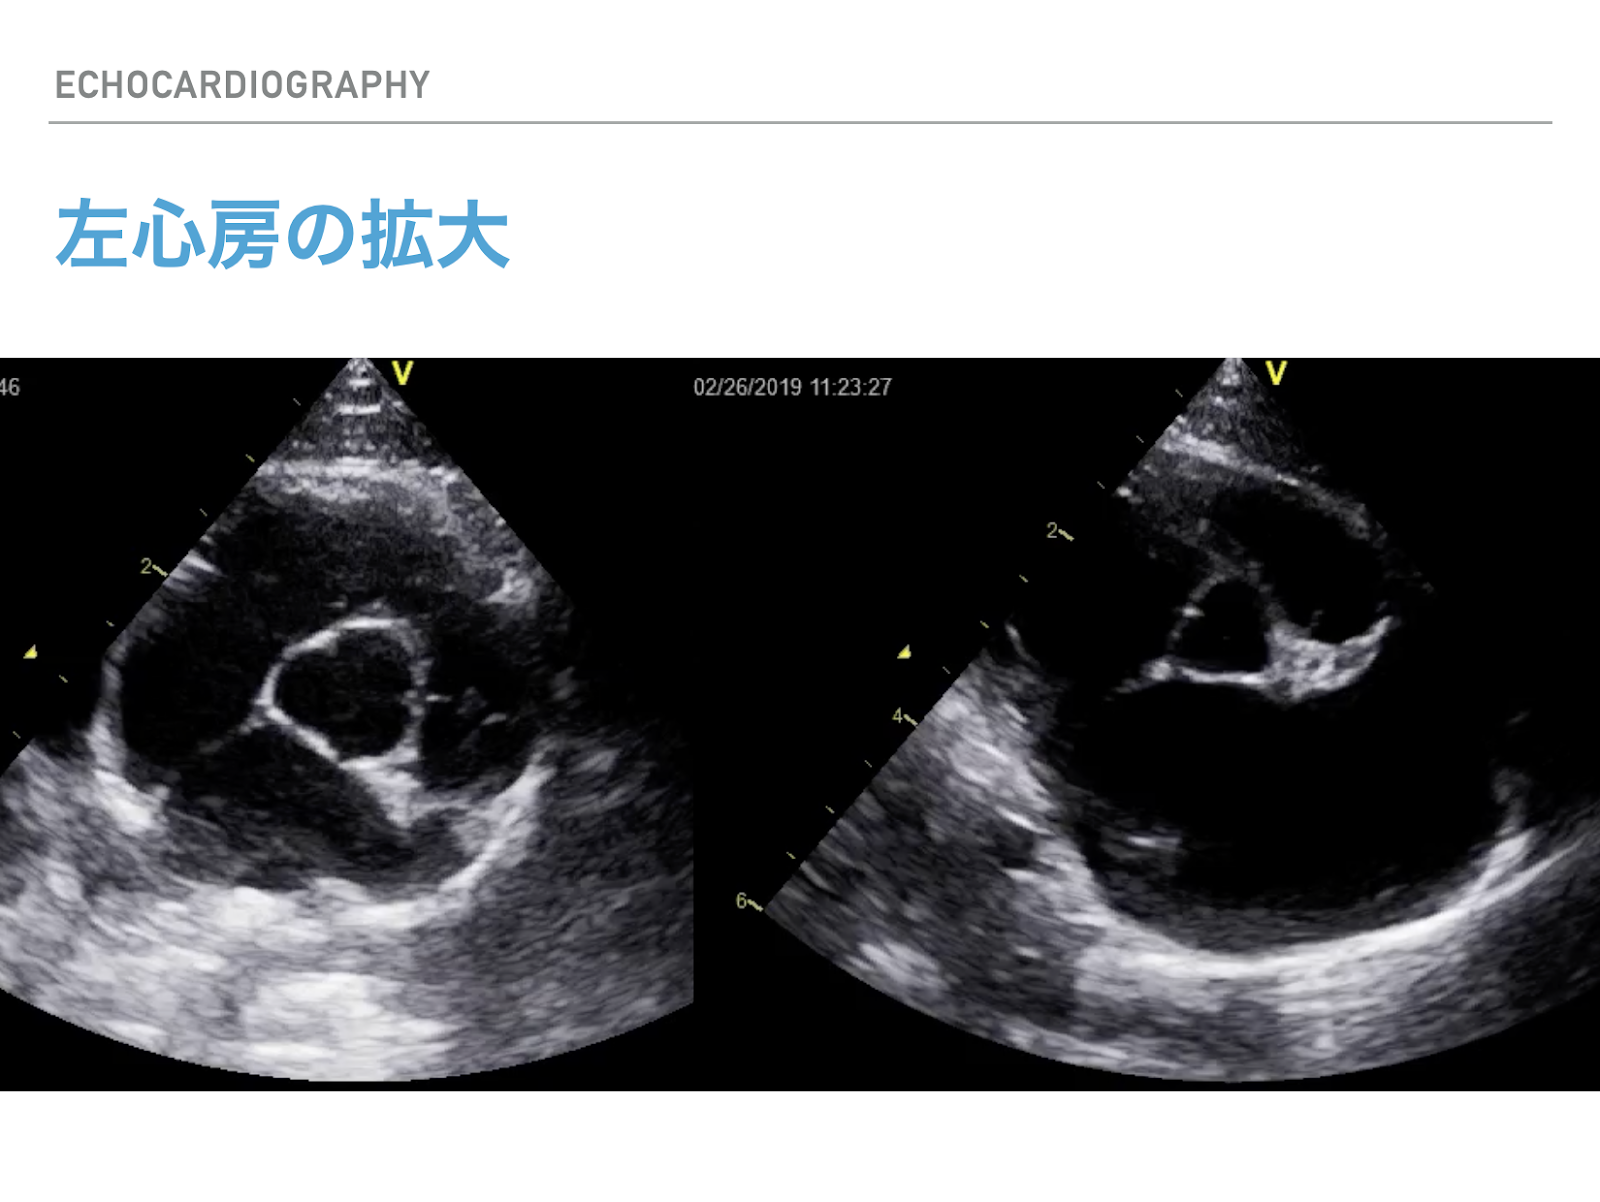

写真のような左心房の拡大が起こると、恐ろしい心不全の症状が出ます。息が苦しくなったり、突然血栓が詰まって後ろ足が動かなくなったり…この状態まで来てしまうと命を救うことが大変難しくなってしまいます。

診断には超音波診断装置を使いますが、猫の診断は熟練した技術と知識が必要です。動物医療センター白金台では、最新の心臓病専用超音波診断装置を備えており、日曜日と月曜日に、日本獣医循環器学会専門認定医の井口の診察が受けられます。心臓病でお困りの方は是非ご相談ください。